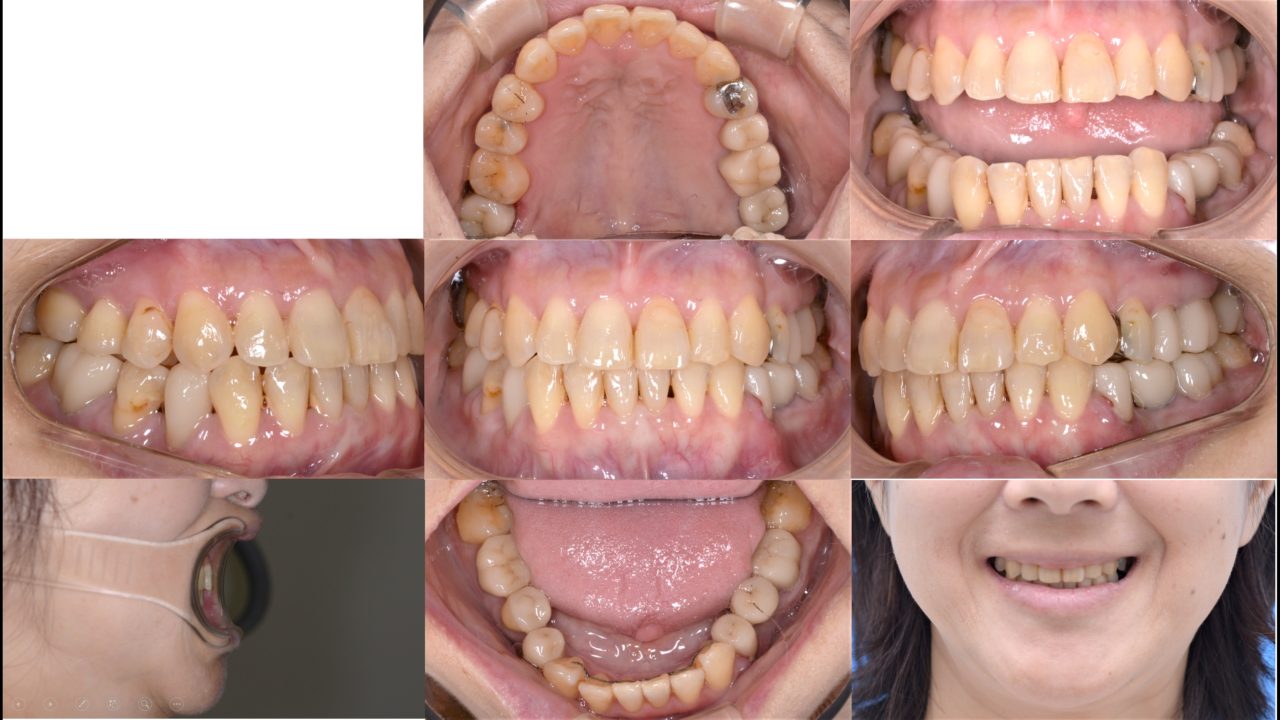

Before

| 主訴 | 奥歯で噛みにくい 奥歯の冠がよく外れる |

| 診断 | 両側アングルクラスⅢ叢生 |

| 矯正方法 | 矯正用インプラントを伴うマルチブラケットシステム |

| 矯正期間 | 19か月 |

| 費用 | 730,000円(税別) |

| 調整料 | 5,000円(税別) |

| 備考 | 以前から当院に通院されている方で定期的に奥歯にトラブルを起こしていました。 下顎奥歯が左右ともに傾斜しており、いわゆる「噛み合わせが悪い」状態でした。 20年後までの歯のトラブルを考えて、噛み合わせと昔に治療した冠を全てコーディネートする フルマウスリコンストラクションをすることになりました。 歯の欠損があったので、2本はインプラントをしました。 矯正治療終了後、セラミックによる補綴治療を行い、噛み合わせのしっかりした状態を作りました。 しっかりメインテナンスをできるだけ再治療のない状態を目指します。 |